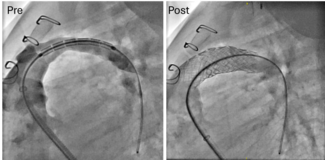

A 53-year-old man with a history of atrial fibrillation underwent a successful antral pulmonary vein isolation. After 6 months of follow-up, he referred for exertional dyspnea. Computed tomography revealed a severe pulmonary vein stenosis of...